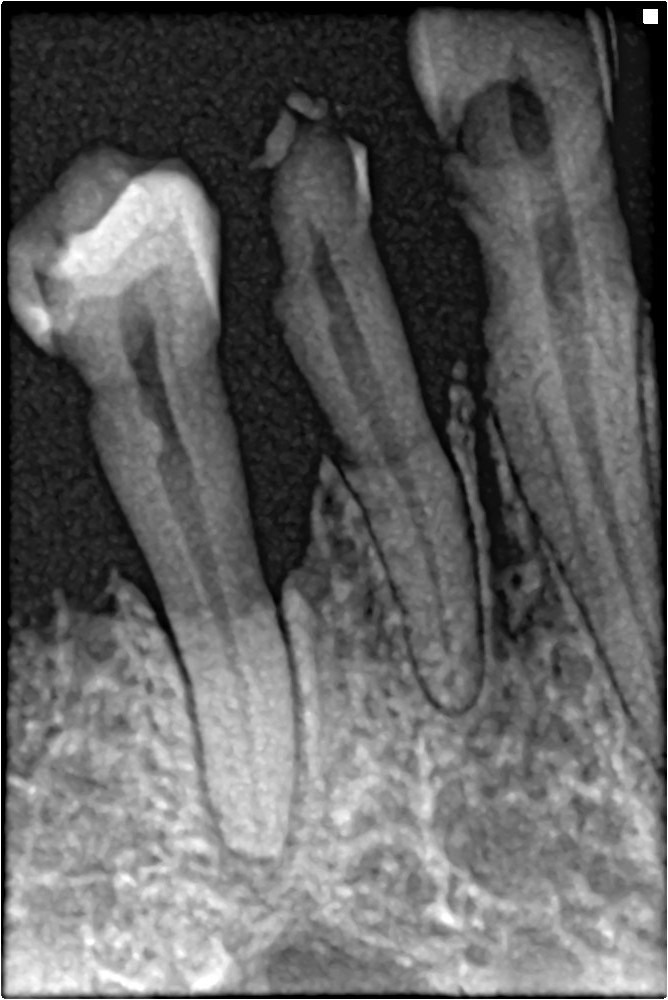

Periapical X-rays show the entire tooth, from the crown to the root, and can diagnose issues such as abscesses, cysts, or impacted teeth (see Figure 15). Bitewing X-rays are used to detect cavities between teeth, to evaluate the health of the teeth and gingiva, and to evaluate periodontal bone loss caused by gingival disease (see Figure 16). Panoramic X-rays provide a broad view of the entire mouth, useful for assessing the position of teeth, especially wisdom teeth, and detecting tumors or other abnormalities (see Figure 17).

Figure 15. Periapical X-Ray |

![]() |

Periapical X-ray: Dental radiograph showing bone loss in a patient who consumes two packs of cigarettes. |

Source: Shaimaa Abdellatif. https://creativecommons.org/licenses/by-sa/4.0/deed.en |